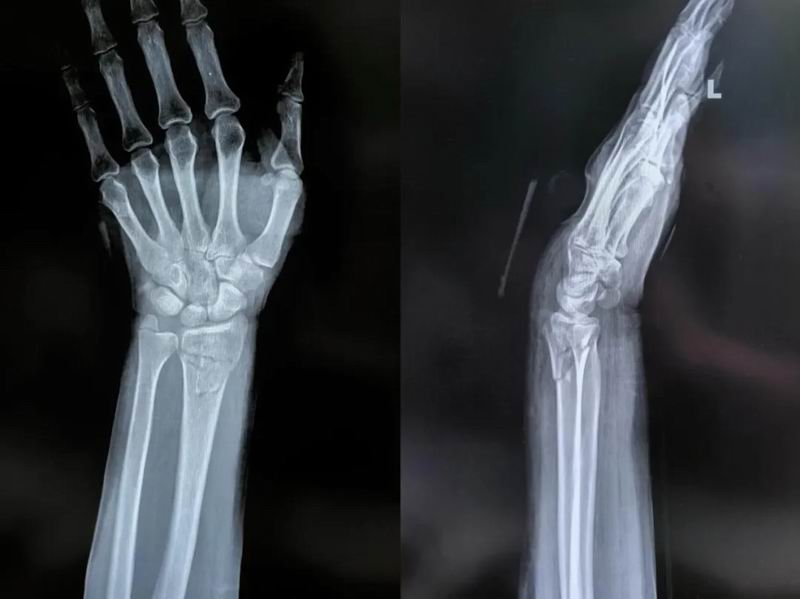

手法复位术(又称闭合复位)是一种非手术治疗方法,医生通过特定的手法技巧,在不切开皮肤的情况下将移位的骨折端重新对位。相比手术治疗,手法复位具有创伤小、恢复快、并发症少、费用低等优势,是大多数简单桡骨远端骨折的首选治疗方法。

患者手法复位后

桡骨远端骨折手法复位术是一门融合了医学知识和手工技巧的“艺术”,经验丰富的骨科医生往往能在几分钟内完成这一“神奇”的复位过程。对于患者而言,了解这一过程有助于缓解治疗焦虑,更好地配合医生完成治疗和康复。成功的治疗不仅依赖于医生的技术,也需要患者的坚持和耐心。